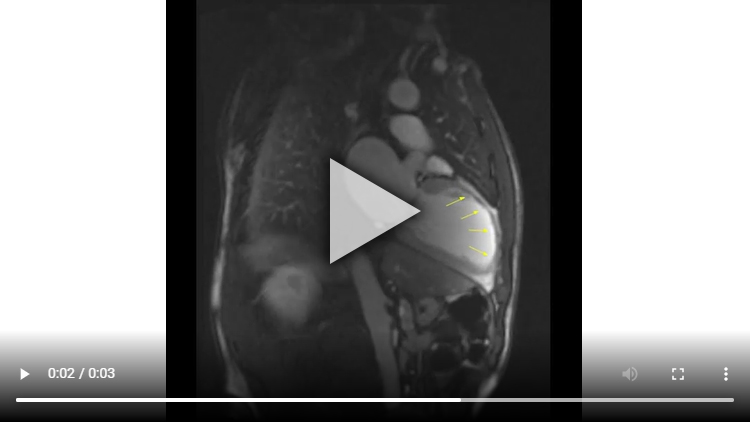

Figure 1B : Séquence Ciné-IRM - Coupe 2 cavités

Présence d’un VG dilaté avec VTD VG mesuré à 119 ml/m2 associé à une large hypokinésie sévère, voire akinésie dans certains segments, de toute la paroi antéro-septo-apicale et débordant sur la paroi apico-latérale.

Altération de la FEVG mesurée à 33% après segmentation VG.

Aucun thrombus intra-VG n’est visualisé sur ces séquences de ciné-IRM.